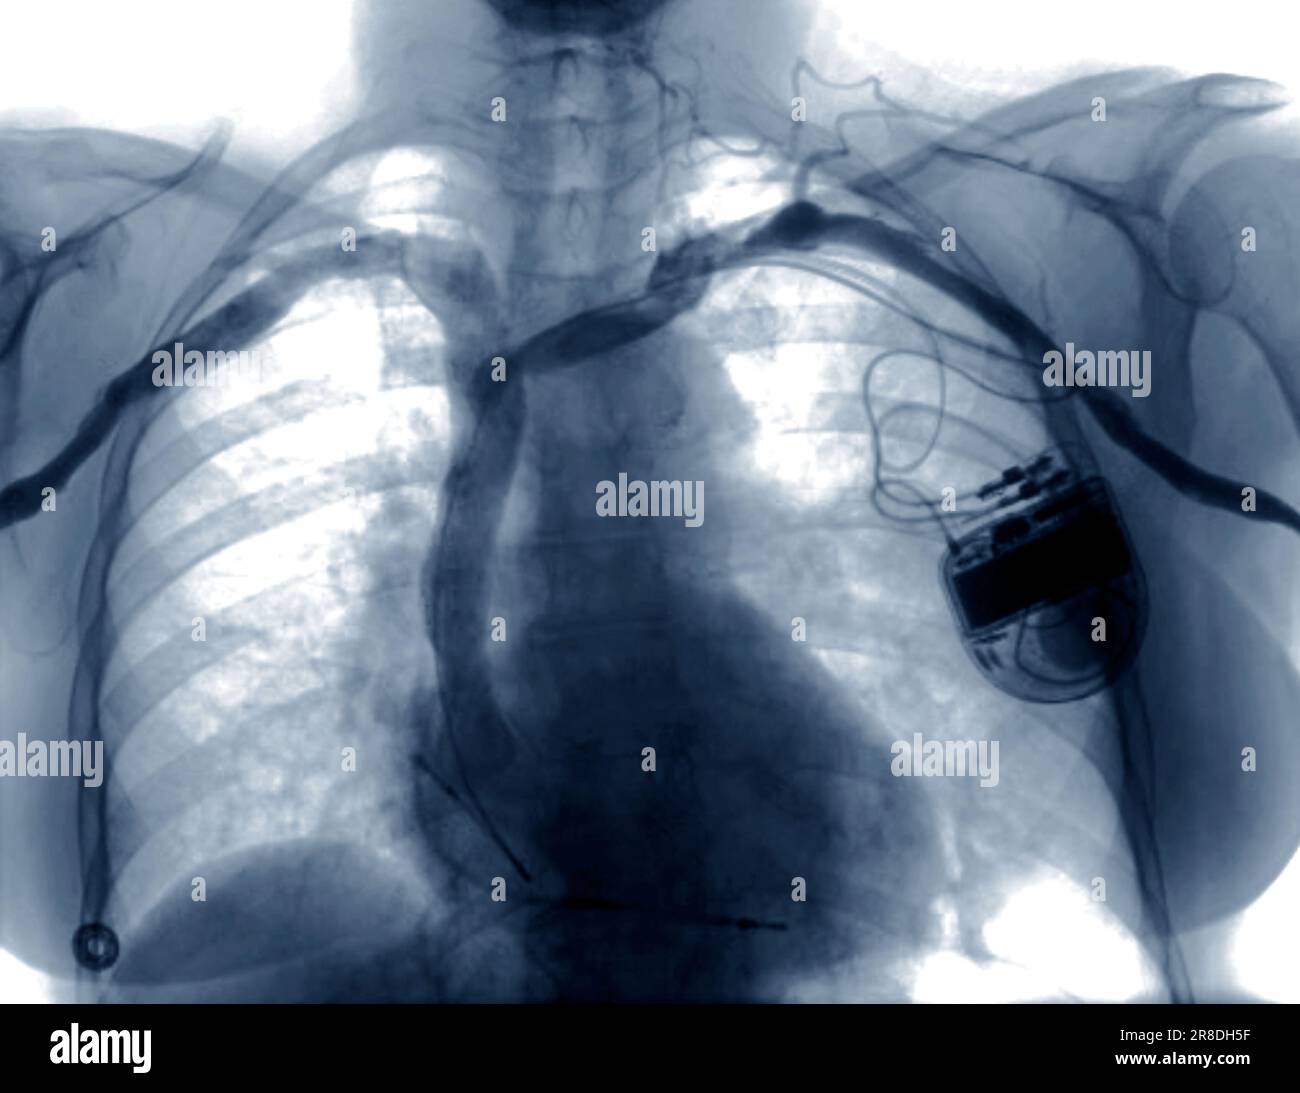

CXR PA view reveals defibrillator on the left chest, RV defibrillator External Defibrillator Cxr Pacemakers that pace the heart during periods of bradycardia. There are two types of cardiac conduction devices (ccd's): Implantable cardioverter defibrillators (icds) have a similar appearance to pacemakers. Aicds are common cardiac devices designed for both patient monitoring and. Pacemakers can be distinguished from implantable cardioverter defibrillators radiographically by absence of shock coil on right ventricle (rv) lead. Almost all. External Defibrillator Cxr.

Xray of chest with defibrillator Stock Photo Alamy External Defibrillator Cxr Implantable cardioverter defibrillators (icds) have a similar appearance to pacemakers. Pacemakers that pace the heart during periods of bradycardia. Pacemakers can be distinguished from implantable cardioverter defibrillators radiographically by absence of shock coil on right ventricle (rv) lead. Aicds are common cardiac devices designed for both patient monitoring and. Almost all of the patients with implanted cardiac devices such as.. External Defibrillator Cxr.